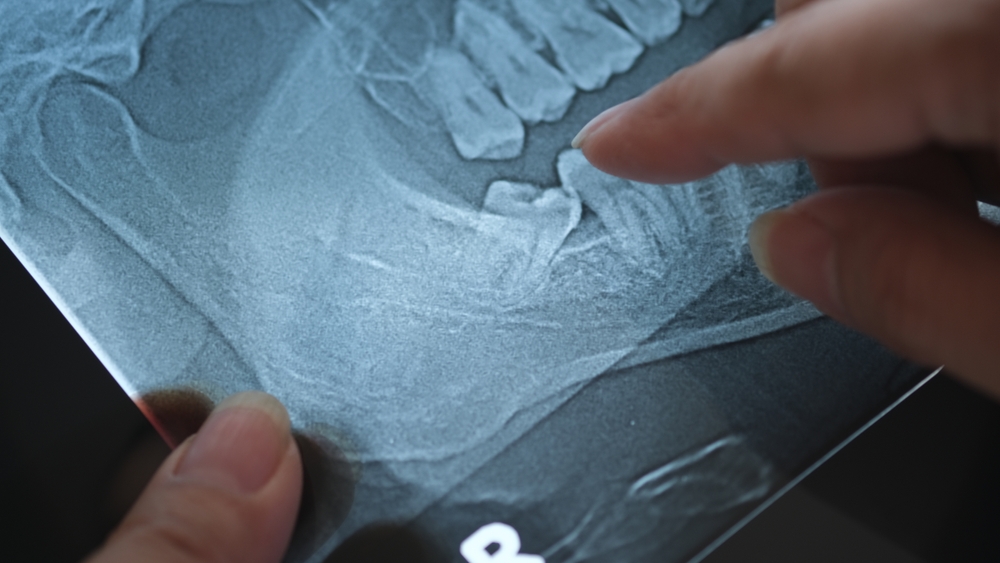

To remove the wisdom tooth, your dentist will open up the gum tissue over the tooth and take out any bone that is covering the tooth. He or she will separate the tissue connecting the tooth to the bone and then remove the tooth. Sometimes the dentist will cut the tooth into smaller pieces to make it easier to remove.